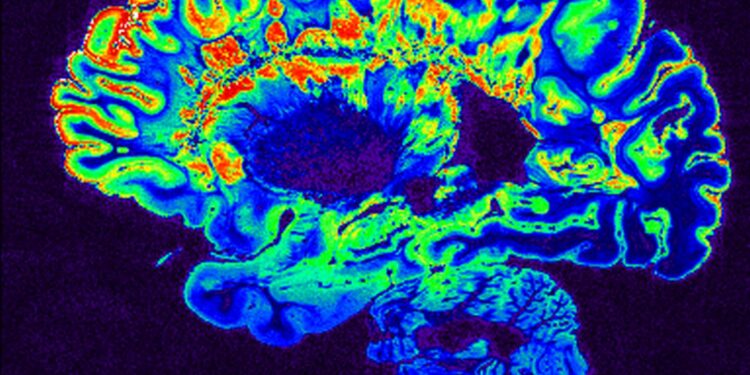

Η σκλήρυνση κατά πλάκας (ΣΚΠ) συχνά αναγνωρίζεται μόνο μετά την εμφάνιση αδιαμφισβήτητων νευρολογικών προβλημάτων, όπως αλλαγές στην όραση ή την ισορροπία. Ωστόσο, μια νέα μελέτη από το Πανεπιστήμιο της Βρετανικής Κολομβίας (UBC) υποδηλώνει ότι το σώμα μπορεί να σηματοδοτεί προβλήματα πολύ νωρίτερα.